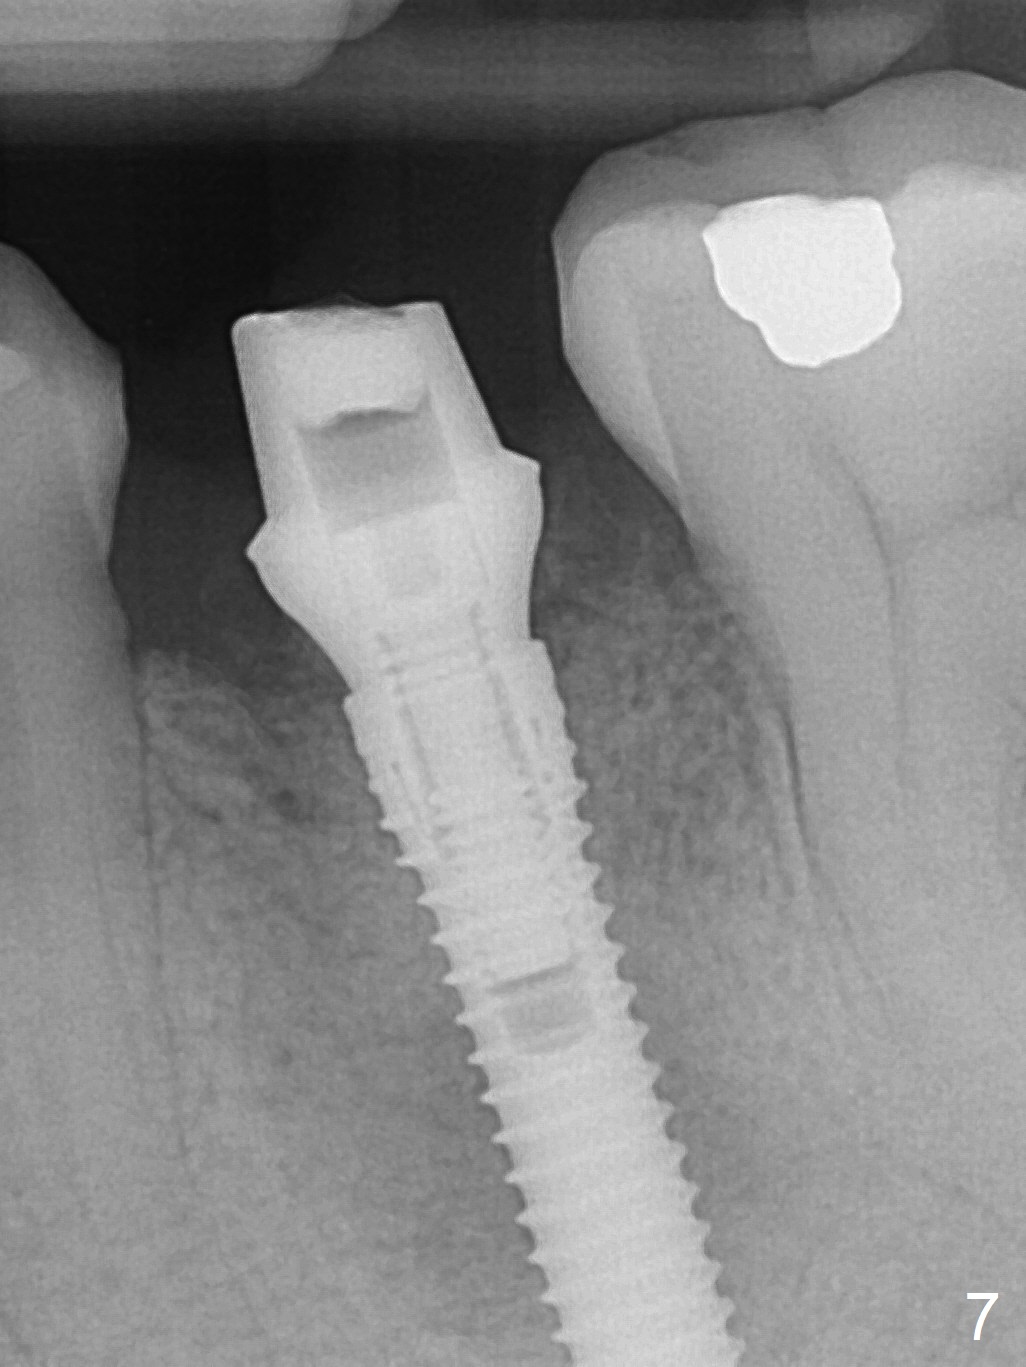

Extraction of the lower left 2nd premolar with vertical fracture (Fig.1,2 >) is easy because of peri-radicular radiolucency.  The apical end of the osteotomy is not shown with a 2 mm pilot drill (Fig.3) or a 3.8x18 mm implant (Fig.4) in place.  It appears that the implant is not placed deep enough.  Following 3-4 more turns of the implant and placement of a 5.5x4(3) mm abutment (Fig.5 A), allograft is placed (*).  A postop panoramic X-ray is taken (Fig.6); the osteotomy could have been deepened to reduce the possibility of periimplantitis.  Retrospectively, the panoramic X-ray should be taken after use of the pilot drill. The bone around the implant appears to have regenerated 4 months postop (Fig.7,8).  Bone density appears to continue increasing 9 months postop (i.e., 4.5 months post cementation, Fig.9).  Bone loss is minimal 2 years post cementation (Fig.10).